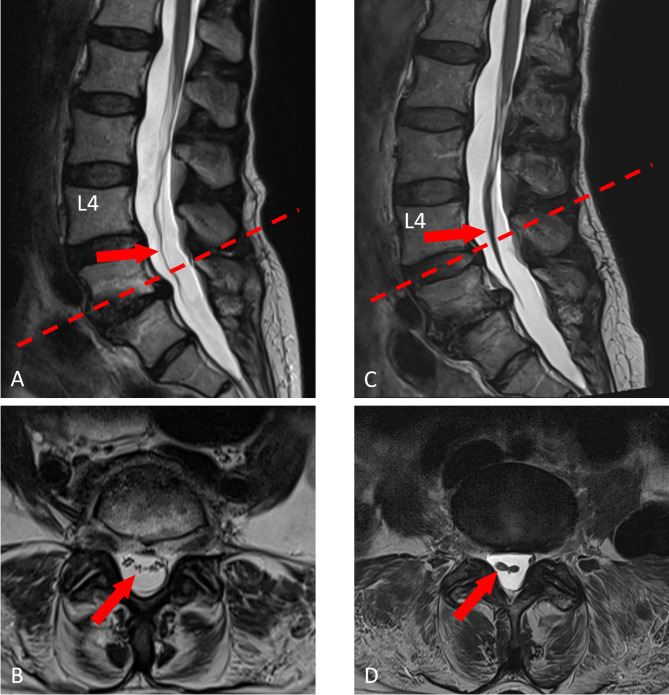

Case presentation: Two cases from our tertiary spine center who sustained conus medullaris and cauda equina syndrome following ESI in a secondary care setting not affiliated with our institution. Both patients received ESI for the treatment of chronic lower back pain without sciatica and any reported neurological impairment prior to the injection. In both Case 1 (F, 72yrs) and Case 2 (F, 72yrs), ESI was administered without imaging-guidance and without pre-interventional lumbar MRI. We assessed both patients by thorough neurological examination, comprehensive neuroimaging, neurophysiology, and neuro-urological assessments. Case 1 had cauda equina syndrome, arachnoiditis was diagnosed from lumbar MRI. Case 2 had conus medullaris syndrome probably related to a reported accidental dura puncture. Symptoms of lumbosacral sensory impairment partly recovered, motor symptoms recovered, but neurogenic lower urinary tract and bowel dysfunction persisted. One patient still requires intermittent self-catheterization, while the other patient suffers from bowel dysfunction at 2-yr follow up.